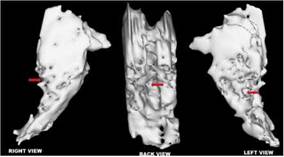

Preservation of intracranial structures

A striking finding was the preservation of intracranial structures both in the brainstem and cerebral hemispheres, which was observed nine months after cardiac arrest resulting in severe brain injury. 13 It has been extensively described that a brain-dead patient lacks cerebral blood flow (CBF). 15,16

Therefore, the first argument against the diagnosis of BD, nine months after the initial diagnosis is the preservation of intracranial structures. Shewmon has reported a series of brain-dead patients with extended somatic survival. 23-25 He expressly referred to Repertinger et al.'s case of a 4-year-old child diagnosed as brain-dead after bacterial meningitis and was then put on a ventilator for 19 years. The autopsy revealed a 750 g calcified intracranial spherical structure and a calcified shell containing grumous material and cystic spaces with no recognizable neural elements grossly or microscopically. 26 Nothing similar was found in this patient's MRI sequences, despite a vast brain insult. Hence, this fact contradicts BD diagnosis in this patient. 13,14,27

As previously noted, Jahi McMath's mri demonstrated a large lesion in the pons. Hence, several reasons might explain the intermittent conscious responses in this patient, including the relative intactness of the upper brainstem, thalamus, and cortex and the partial sparing of the mesopontine tegmental reticular formation. She might also have preserved its connections to the thalamocortical or its ventral pathway to the cortico-cortical projection systems, and parts of the associative cerebral cortices. 6,13,42 Therefore, Walter et al. were not far from the truth when they hypothesized that “a brainstem lesion may cause an apneic total locked-in syndrome, a rare syndrome with preserved capability for consciousness, mimicking brainstem death.”4,45